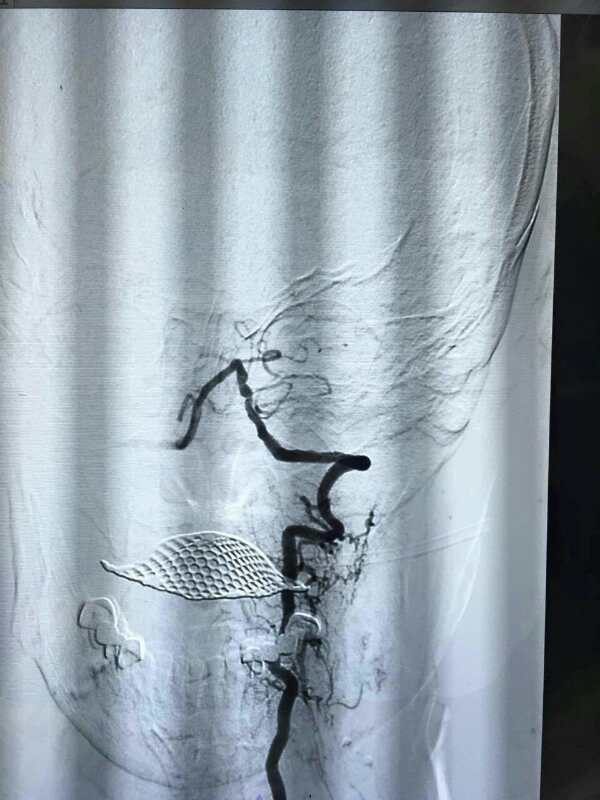

患者迅速被送入介入中心,介入中心王平主任医师以最快的时间完成全脑血管造影.造影显示:患者基底动脉起始段完全闭塞,与术前诊断一致。由于此类患者预后极差,尽快开通血管兴许还有一线生机,游洋主任、王平主任医师立即为患者行颅内闭塞血管支架取栓治疗,取栓后完全闭塞的血管再次开通,手术仅耗时一小时,术后第二日患者意识恢复,四肢肌力III级,于神经内科继续进行专科治疗。